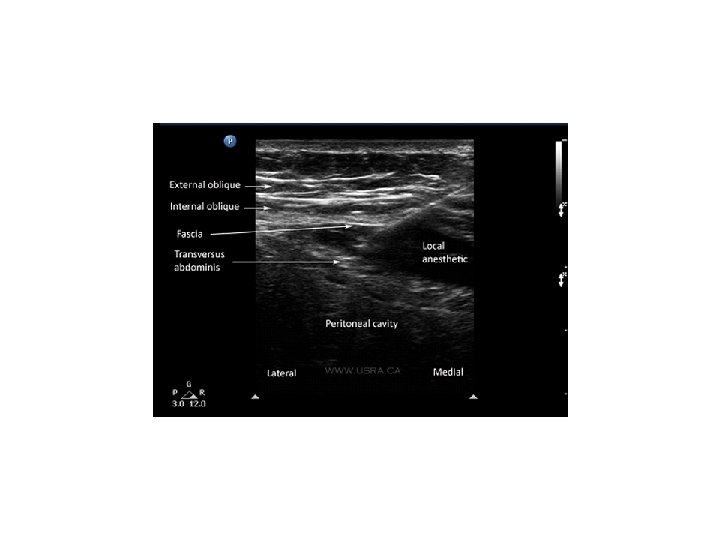

Transversus Abdominis Plane (TAP) Block • Provides analgesia to the skin and muscles of the antero -lateral abdominal wall and parietal peritoneum. Does not block visceral pain. • Goal of the block is to place LA between the internal oblique and transversus abdominis muscle layers resulting in the interruption to the innervation of the abdominal skin, muscles and parietal peritoneum. • Administered by landmark, ultrasound guided by anesthesia or direct visualization by the surgeon • Single injection vs. catheter bolus. Bupivicaine, Ropivicaine, and Levobupivicaine commonly used. • Used for patients undergoing lower abdominal surgery; appendectomy, c-sect, hernia repair, abdominal hysterectomy and prostatectomy.

Transversus Abdominis Plane (TAP) Block • Triangle of Petit: bounded by the latissimus dorsi posteriorly, the external oblique anteriorly and the iliac crest inferiorly. • Needle is inserted perpendicular to all planes looking for the tactile sensation of 2 pops. First indicates penetration of the external oblique fascia into the plane between external and oblique muscles. Second pop signifies entry into the plane between internal oblique and transversus abdominis muscles.